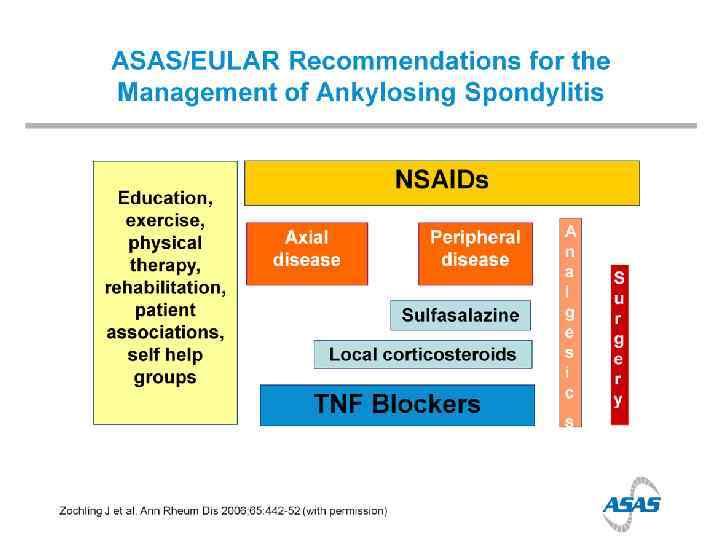

Treatment